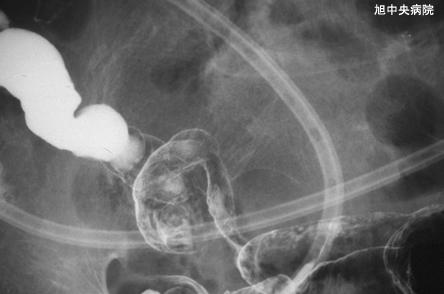

일레우스 증상을 보인 허혈성 소장염의 수술예 (증례제시:치바현 아사히시 아사히중앙병원)

염증성 및 궤양성질환/허혈성 장염(혈전증 포함)

소장/회장

X-P

40이상